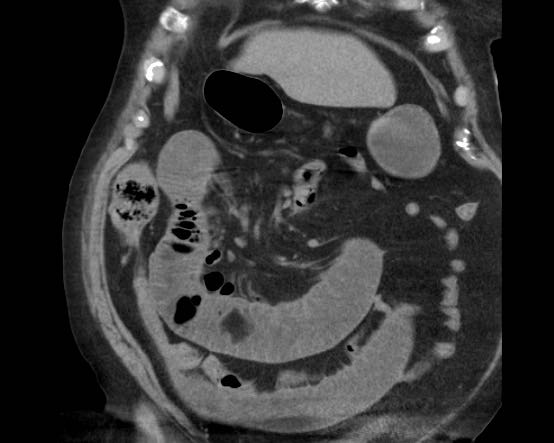

Đây là hình ảnh điển hình của tắc ruột do sỏi mật.

Lưu ý mức độ khó khăn khi phát hiện viên sỏi không vôi hóa.